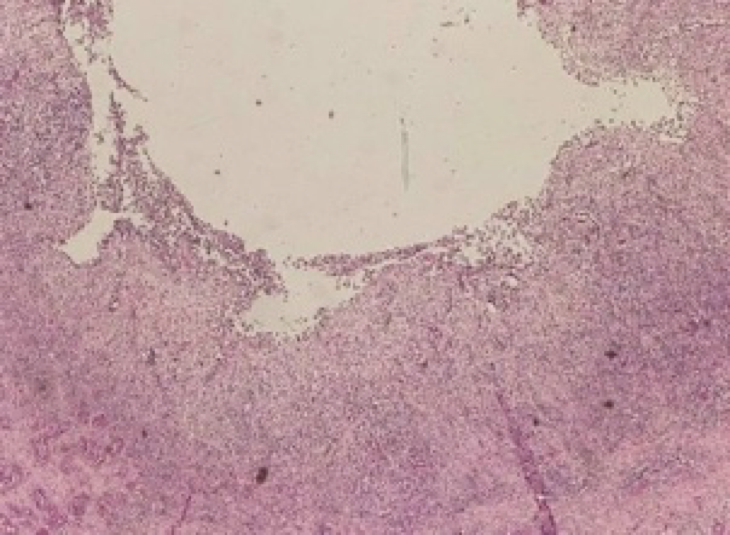

What is this an image of?

Normal breast